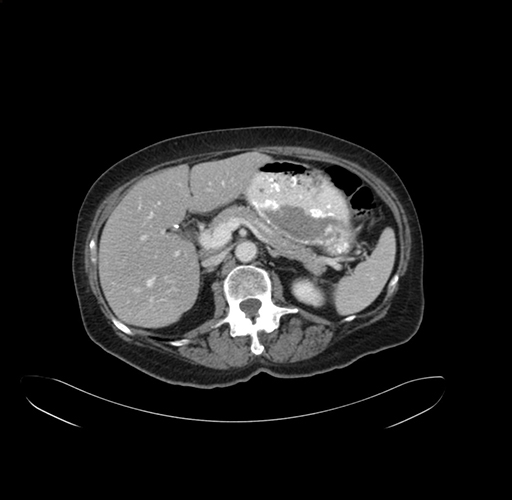

Pre-Chemo: Axial Venous

Axial Venous